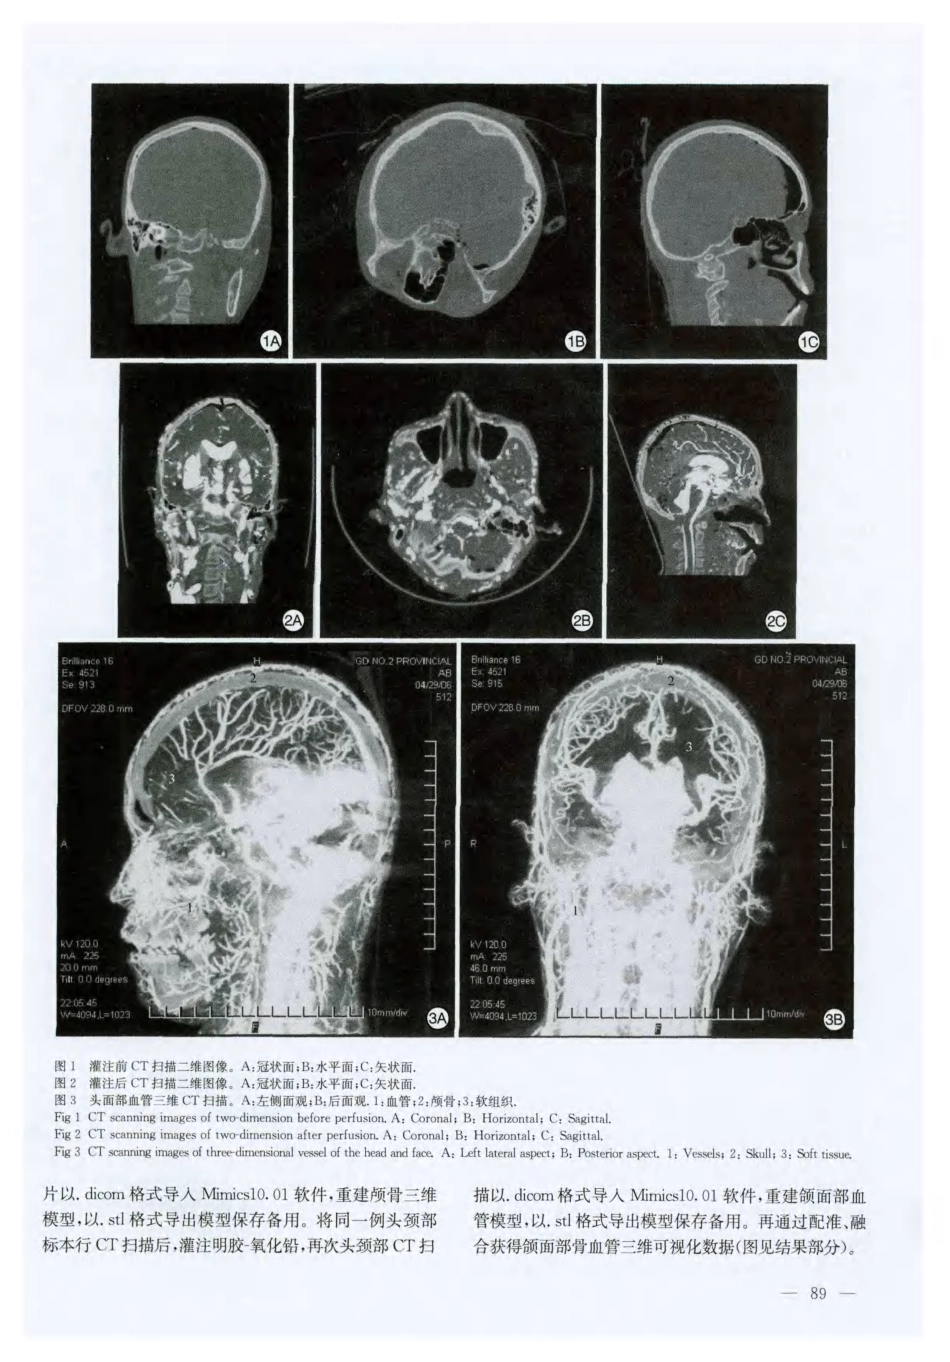

CHINESEJOURNALOFANATOMYVo1.34No.12011解剖学杂志2011年第34卷第1期颌面部血管的三维可视化王爱平李严兵△谢巍洪丽周小兵彭田红吕运成(南华大学医学院人体解剖学教研室,衡阳421001)摘要目的:探讨人体颌面部血管数字化的方法,对颌面部血管进行三维可视化研究。方法:选人体新鲜头颈部标本,未经灌注及灌注后,通过CT连续扫描获得数据集,运用Mimics软件对颌面部血管进行三维重建,并对相关结构进行解剖学观察。结果:该数字化可视模型可以多色彩、透明或任意组合显示,可任意旋转和切割,并从任意角度和方式进行观察,同时清晰地显示出颌面部血管的解剖学结构特点,具有形象直观的特点。结论:颌面部血管的三维可视化,为临床颌面部整形术的手术设计、制定术前方案及应用解剖学基础研究等提供新的方法。关键词颌面部血管;三维重建;可视化3-DvisualizationofbloodvesselinmaxillofacialregiOnWangAiping,LiYanbin,XieWei,HongLi,ZhouXiaobing,PengTianhong,LnYuncheng(DepartmentofAnatomy,MedicalSchoolofUniversityofSouthChina,Hengyang421001,China)AbstractObjective:Toexplorehowtobuildvisualizationdigitalmethodofmaxillofacialregion’Sbloodvessel,andstudy3一Dvisualizationofmaxillofacialregion’Sbloodvesse1.Methods:Thedatasetsoffreshadulteephal—neckspecimensweregotbyscanningcontinuouslywithCTbeforeperfusionandafterfillingconstrastmediumofgelatin-leadoxidethroughcommoncarotidartery,andanatomicstructureswerebuiltbyusingsoftwareofMimicsandobserved.Results:The3-Dreconstruc—tionmodelwasdisplayedfromdifferentcolors,transparenceanddifferentaspects,whichcouldbewillfullyrotatedandcut,anditwasalsoviewedfromdiferentaspectsanddifferentlayers.Simultaneously,themodelperfectlydisplayedtheanatomiefeatureofmaxillofacialregion’Sstructure.Conclusion:The3-Dvisualizationimagesofmaxillofacialregion’Sarteryprovideanewmethodforanaplastyofmaxillofacialregion’Soperationaldesigning,pre-operationplanandbasalanatomicalteaching,etc.Keywordsbloodvessels;maxillofacialregion;3-Dreconstruction;visualization颌面部是人体美表现最为集中的部位,人体对其美观的重视远远超过身体其它部位。因此颌面部缺损畸形的即刻修复,已成为现代口腔颌面外科,整形美容外科,口腔矫形科等领域的研究课题[1]。颌面部整形美容由于其手术的复杂性和精确性要求,一直是整形美容界公认的较为棘手的领域。采用多学科合作,多领域技术的相互配合的方法,是颌面部整形美容的发展趋势l_3]。与此同时,临床手术的成功开展对基础研究者也提出了更高的要求,随着标本来源的日趋减少,构建颌面部血供的精细解剖图像,特别是三维立体的形态资料有助于展示颌面部主要血管的走行和空间位置关系,有助于临床的缺损修复及解剖学学习。本研究应用现代计算机软件建立颌面部血管数字解剖学模型,为临床颌面部整形术的手术设计、制定术前方案及解剖学教学提供了形态学依据。*湖南省教育厅科研基金(09C836);湖南省科技厅科研基金(2O09FJ3129)第1作者E-mail:gwaiping@yahoo.tom.cn△通讯作者,E-mail:hn|ybup001@163.corn收稿日期:201005~10;修回日期:2010—1028—88—1材料和方法1.1材料新鲜成人头颈部标本2例,所有标本头颈部均无畸形、骨折、肿瘤及破损。1.2未灌注前行CT扫描取新鲜正常成人头颈部标本,行连续薄层CT扫描,扫描条件为:管电压恒定120kV,电流250mA,扫描范围从颅顶至第3颈椎水平。参数:层厚1.0mrn,矩阵512×512,显示野为250ITlm。将得到的头颈部连续二维断层图像数据,以.dicom格式保存(图1)。1.3明胶一氧化铅灌注后再行CT扫描取行CT扫描后新鲜成人头颈部标本,采用唐茂林等改良的明胶一氧化铅灌注技术经颈总动脉灌注,灌注后再行连续薄层CT扫描,扫描条件与未灌注扫描一致。将得到的头颈部连续二维断层图像数据,以。dicom格式保存(图2、3)。1.4三维重建将正常成人头颈部标本CT扫...